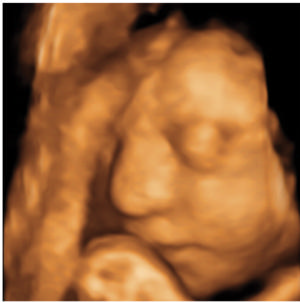

Dr. Levine noted that ultrasound in pregnancy can show the abnormalities associated with congenital Zika infection, but it may take time before these changes are obvious.

"More than one ultrasound or MRI scan in pregnancy may be needed to assess the growth and development abnormalities of the brain," she said.

Figure 3. Images obtained in the case of a 34-year-old woman with confirmed Zika virus infection, initially seen for a rash at 8 weeks of gestation. Fetal head cir¬cumference was in the normal range at 12 and 16 weeks (5.8 cm and 11.9 cm, respectively) but then decreased to the 10th percentile at 22 weeks and was below the 3rd percentile in subsequent imaging examinations. (a–h) US images were obtained at 30 weeks. Head circumference on the axial image (a) measured 24 cm (˂2.3 percentile, corresponding to a gestational age of 26 weeks 3 days). Note the open sylvian fissures and relatively smooth cortex, which are abnormal findings at this gestational age. Oblique axial image (b) shows cerebellar calcifications (seen as the echogenic outer contour of the cerebellar hemispheres) and inferior vermian hypoplasia with associated enlarged cisterna magna. A sagittal transvaginal image (c) shows calcifications in the basal ganglia (arrowheads) and more bulky calcifi¬cation at the gray matter–white matter junction. Another sagittal transvaginal image (d) shows a relatively small corpus callosum (arrows). A coronal image (e) shows cortical and subcortical white matter calcifications in a linear pattern. The gyral pattern is abnormal, which is suggestive of polymicrogyria. A sagittal Color Doppler image (f) shows a stretched appearance of vessels coursing into the posterior fossa. An oblique axial grayscale transvaginal image in the posterior fossa (g) shows heterogeneous material in the confluence of sinuses due to blood clot (arrow). A three-dimensional US image of the face (h) shows a sloping forehead, compatible with frontal lobe hypoplasia. (i) Axial and (j) sagittal fetal MR images obtained at 29 weeks show atrophic frontal lobes, wide sylvian fissures, enlarged posterior fossa, abnormal gyral pattern, prominent cerebrospinal fluid spaces, and inferior vermian hypoplasia. On (i), note the diffuse hypointense and undersulcated cortex, which is suggestive of mineralization and polymicrogyria. The hypoplastic corpus callosum can be seen on the sagittal view (j), as well as the inferior vermian hypoplasia, en¬larged cisterna magna, and heterogeneous signal intensity in the confluence of sinuses. There is a subjectively thin spinal cord. (k) Postnatal axial MR image obtained at 81 days shows small frontal lobes and cortical thickening. The choroid plexi are enlarged. (l) Photograph of the neonate after birth.

High-res (TIF) version